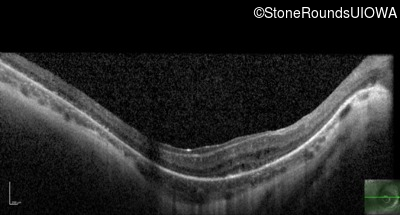

Optical Coherence Tomography - Right - 10/600

Exemplar / OCT Stack

OCT Stack